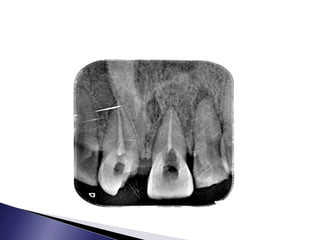

 PATIENT DETAILS: NAME: Mani  AGE/SEX: 35yrs/ male  ADDRESS: Madurai  OP NO: 18- 16418  DATE REPORTED: 05.09.18

• 80.

 Patient reportedto the department with a complaint of pain in the upper front region of the jaw  History of throbbing pain which aggravates on mastication and relieves on medication

• 81.

 History oftrauma before 2 years  There was no relevant medical history  Patient has normal food habits, and brushes twice daily using brush and paste  Patient is alert, cooperative, conscious and well-oriented

• 82.

 Facial symmetrypresent  TMJ is normal  Cervical lymph nodes palpable  There is no extraoral swelling evident

• 83.

 Discoloured 21 Tender on percussion present in 21  swelling evident  abscess evident

• 85.

• 86.

• 87.

 Root canaltreatment in 21